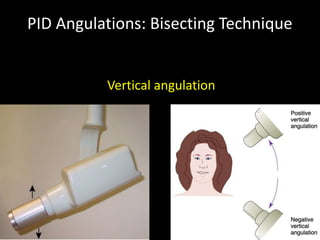

2. The paralleling cone technique provides accurate images with little magnification and no superimposition but is more difficult for patients. The bisecting angle technique is easier for patients but results in more image distortion.